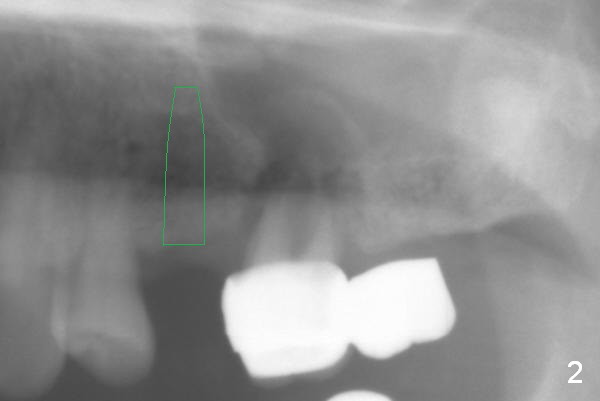

The 72-year-old man will return for #13-15 implantation after that at #2/4 and 28. There is severe wear in the cingula of the upper anterior teeth due to posterior collapse (several missing teeth, residual root and failing restoration, Fig.1). Prior to removal of the cantilever bridge (#14.15), an implant is placed at #13 (Fig.2). If the defect at #14 is too large after extraction, an implant is placed at #15 with an immediate provisional bridge (Fig.3 white line). Otherwise a large implant (possibly Tatum tapered) will be placed at #14 (Clindamycin) with splinted immediate provisional (Fig.4). Allograft is expected for sinus lift at #14 and 15 (Fig.3,4 red circles with Osteogen in 3:1 ratio). For socket preservation at #14, mix equal amount of allograft and Osteogen (Fig.3 pink), followed by Collagen plug (yellow) and the pontic of the provisional bridge. Prepare PRF (3-4 tubes of blood, one of them to be made for a plug).